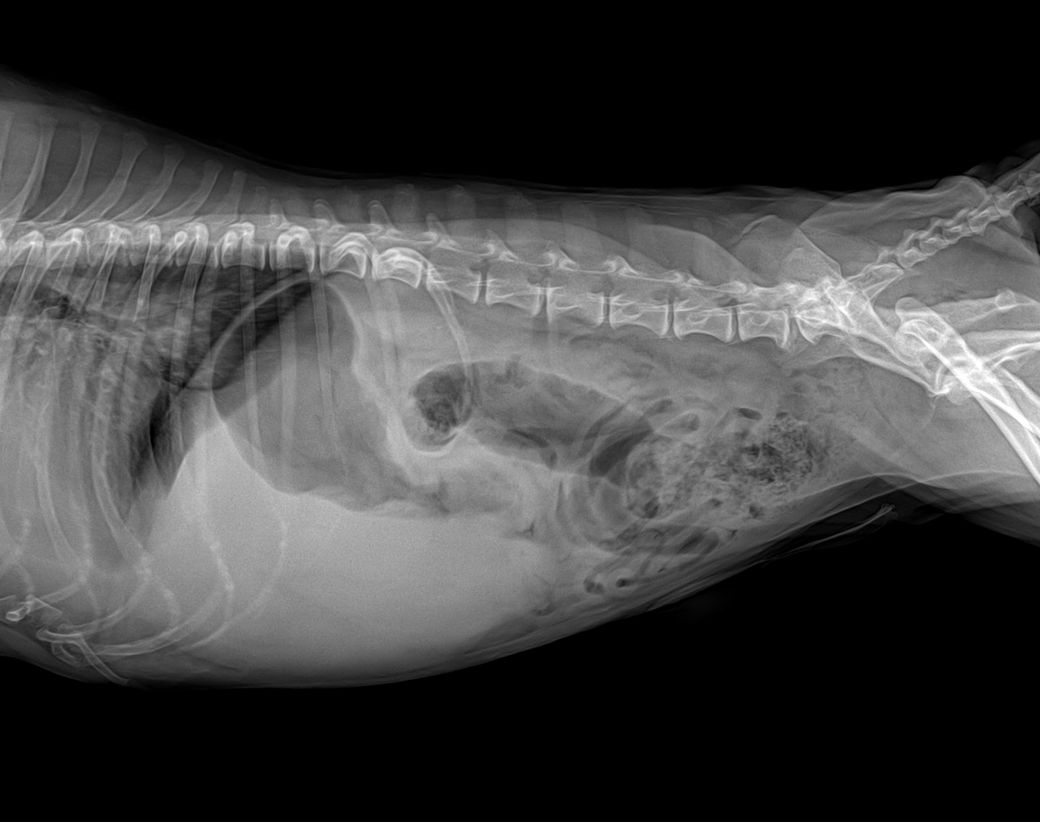

심장도 키기가 매우 크고, 좌심방 돌출이 있으며, 경미하지만 폐수종이 발생한 상태면서, 흉수도 보입니다.

또한 간의 크기가 큰데, 종괴 양상이 보여 간암 가능성이 매우 높아 보이니 복부 초음파 검사와 심장 초음파 검사 모두 필요합니다.